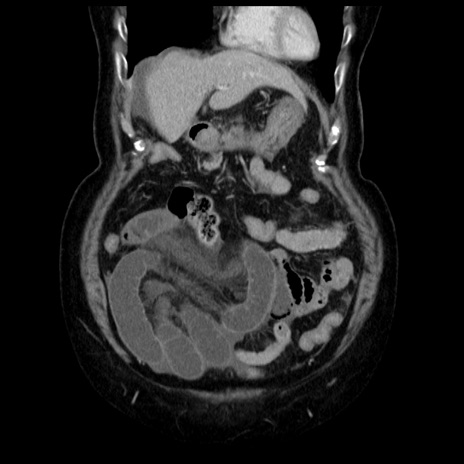

症例13(冠状断像)

【症例】70歳代女性

【主訴】腹痛、嘔吐

【現病歴】15時間程前(昨晩)より腹痛あり。今朝になっても症状の改善なく、嘔吐あり。腹痛も増悪あり、救急外来受診。

【既往歴】子宮癌全摘術後

【身体所見】意識清明、BP 121/72mmHg、P 74bpm、SpO2 100%(RA)、腹部:平坦・軟、腸雑音ほぼ聴取せず。下腹部・心窩部・臍左上に圧痛あり。反跳痛なし。

【データ】WBC 10600、CRP 0.15